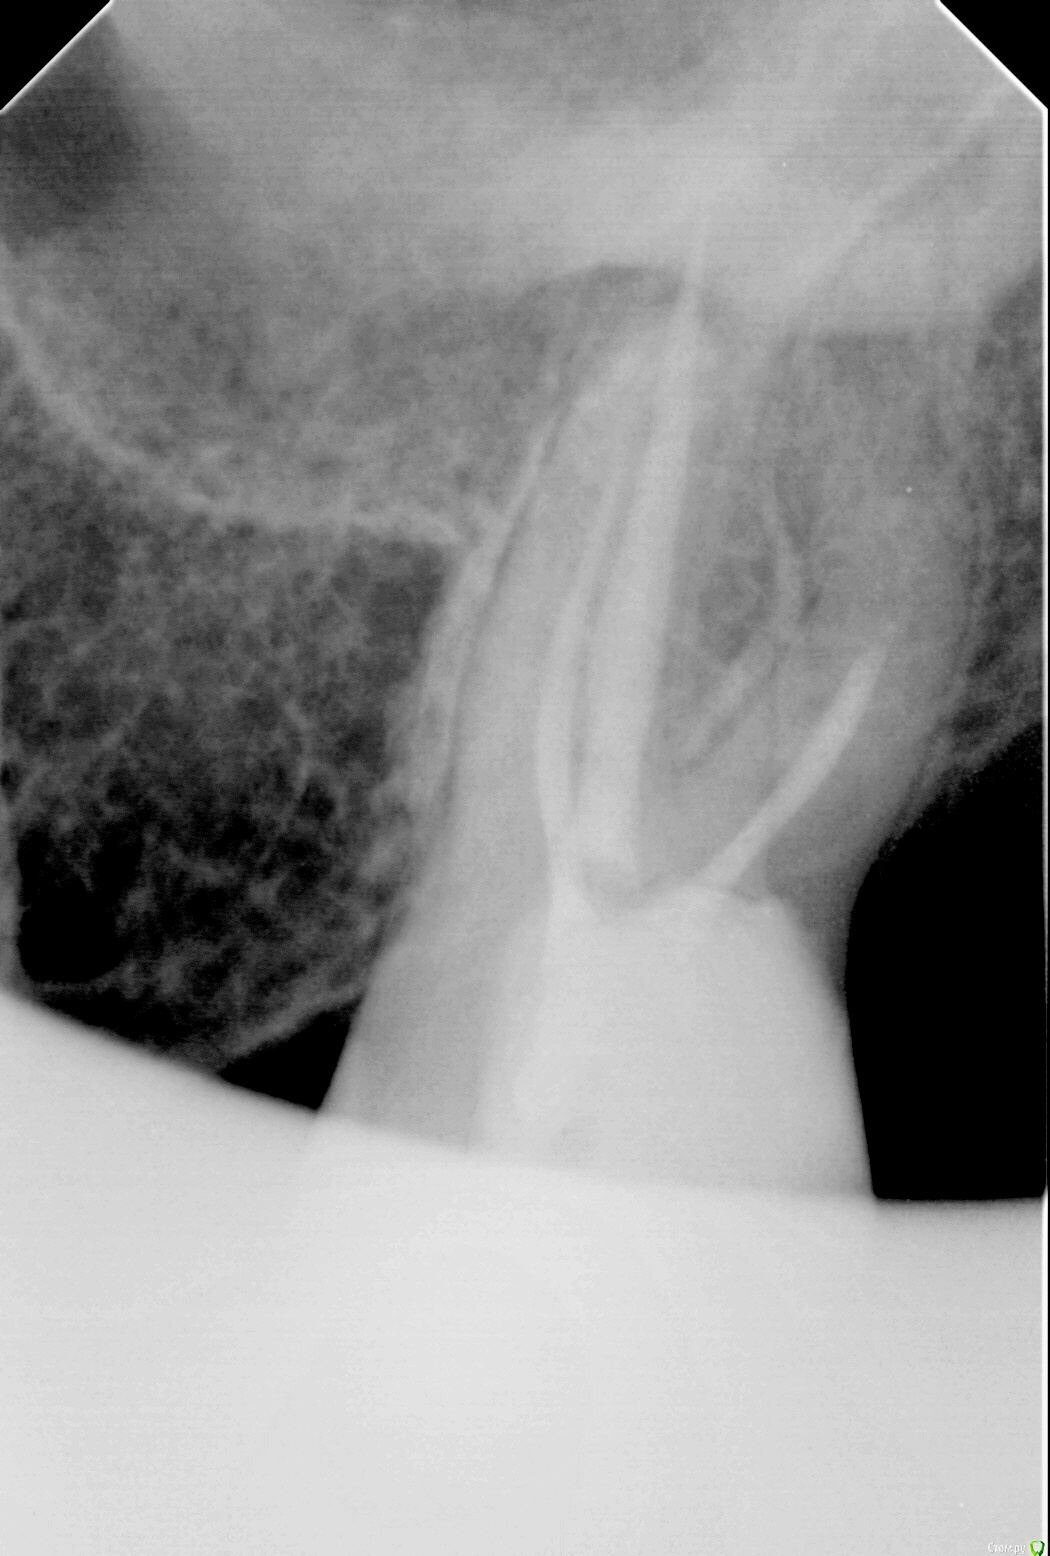

IvanK Опубликовано 2 октября, 2017 Поделиться Опубликовано 2 октября, 2017 "кисты" не увидел, анатомия у зуба сложная. я бы советовал сделать кт, после - принимать решение 2 Ссылка на комментарий

IvanK Опубликовано 2 октября, 2017 Поделиться Опубликовано 2 октября, 2017 панорамный снимок "мутный"..по прицельному - если судить только глядя на снимок - у меня нет показаний к удалению 1 Ссылка на комментарий